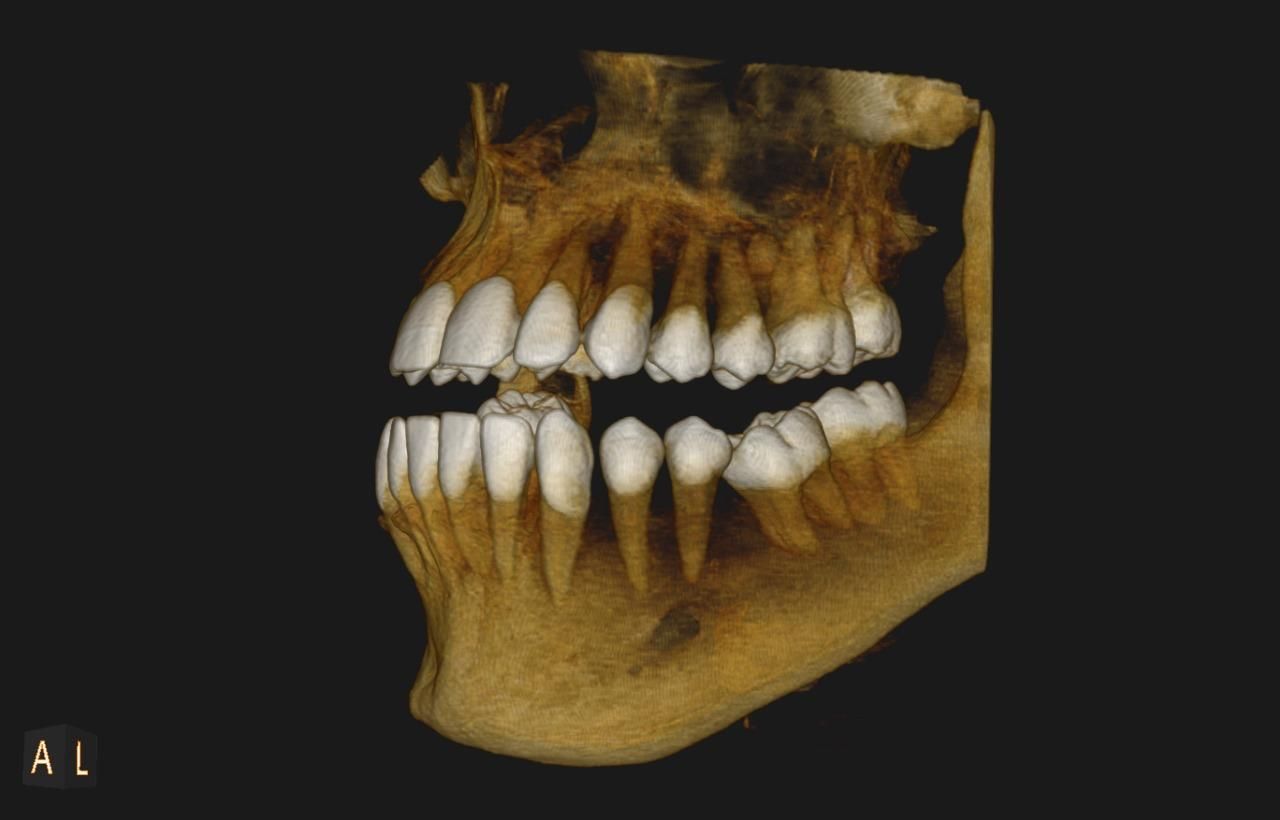

Uno de nuestros principales servicios es la adquisición de imágenes dentales 2D y 3D, fundamentales para un diagnóstico preciso y una planificación adecuada de tratamientos dentales.

Contamos con tecnología avanzada que nos permite obtener imágenes claras y detalladas de la boca y los tejidos circundantes, lo que es crucial para evaluar la salud dental y detectar posibles problemas.